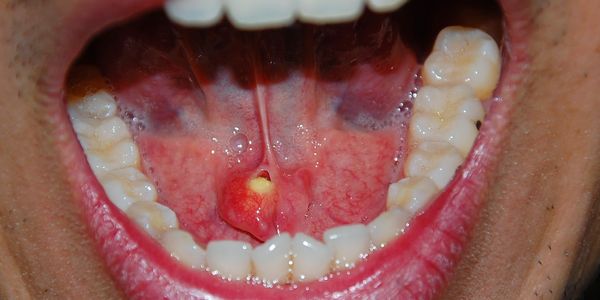

- Presença de pus ou secreção na boca: Sinal de infecção bacteriana.

Sialoadenite

A sialoadenite é uma infecção das glândulas salivares, geralmente causada por bactérias como Staphylococcus aureus.

É caracterizada por dor intensa, inchaço e, frequentemente, febre.

O tratamento inclui antibióticos e medidas para aumentar o fluxo de saliva.